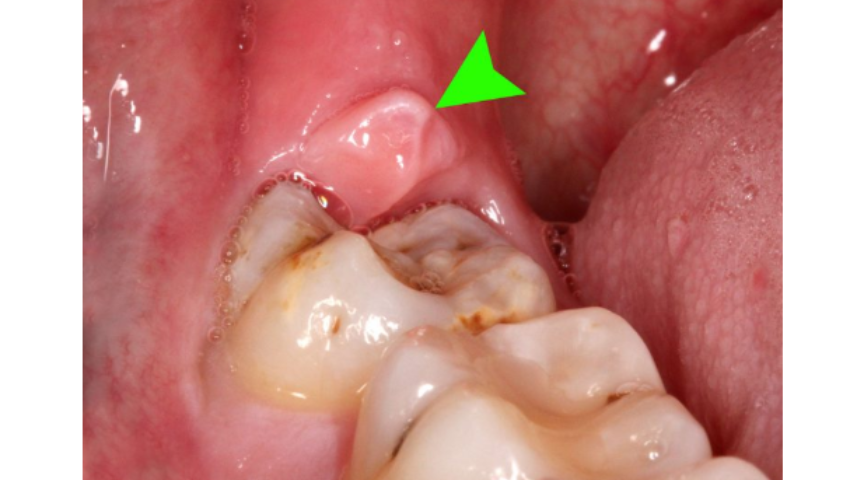

Viêm lợi trùm là bệnh lý thường gặp trong quá trình phát triển của răng khôn. Lợi trùm là phần lợi của người bệnh bao phủ toàn bộ hoặc một phần ở trên bề mặt của răng khôn, gây cản trở đến sự phát triển một cách bình thường của chiếc răng đó.

Hiện tượng lợi trùm răng khôn có thể hiểu là là chiếc răng khôn đó mọc lên bị che lấp một phần bởi lợi, chỉ có thể mọc được một phần ra bên ngoài.

Hay nói cách khác, lợi trùm sẽ làm hạn chế sự phát triển của răng khôn. Hầu hết người mắc phải tình trạng lợi trùm răng khôn là người trưởng thành trong độ tuổi mọc răng khôn.

- Lợi sưng, tấy đỏ: Lợi trùm lên phần mọc răng khôn khi bị viêm sẽ tấy đỏ, sưng khi chạm vào sẽ có cảm giác đau nhức, thậm chí những trường hợp nặng còn xuất hiện nước và mủ.